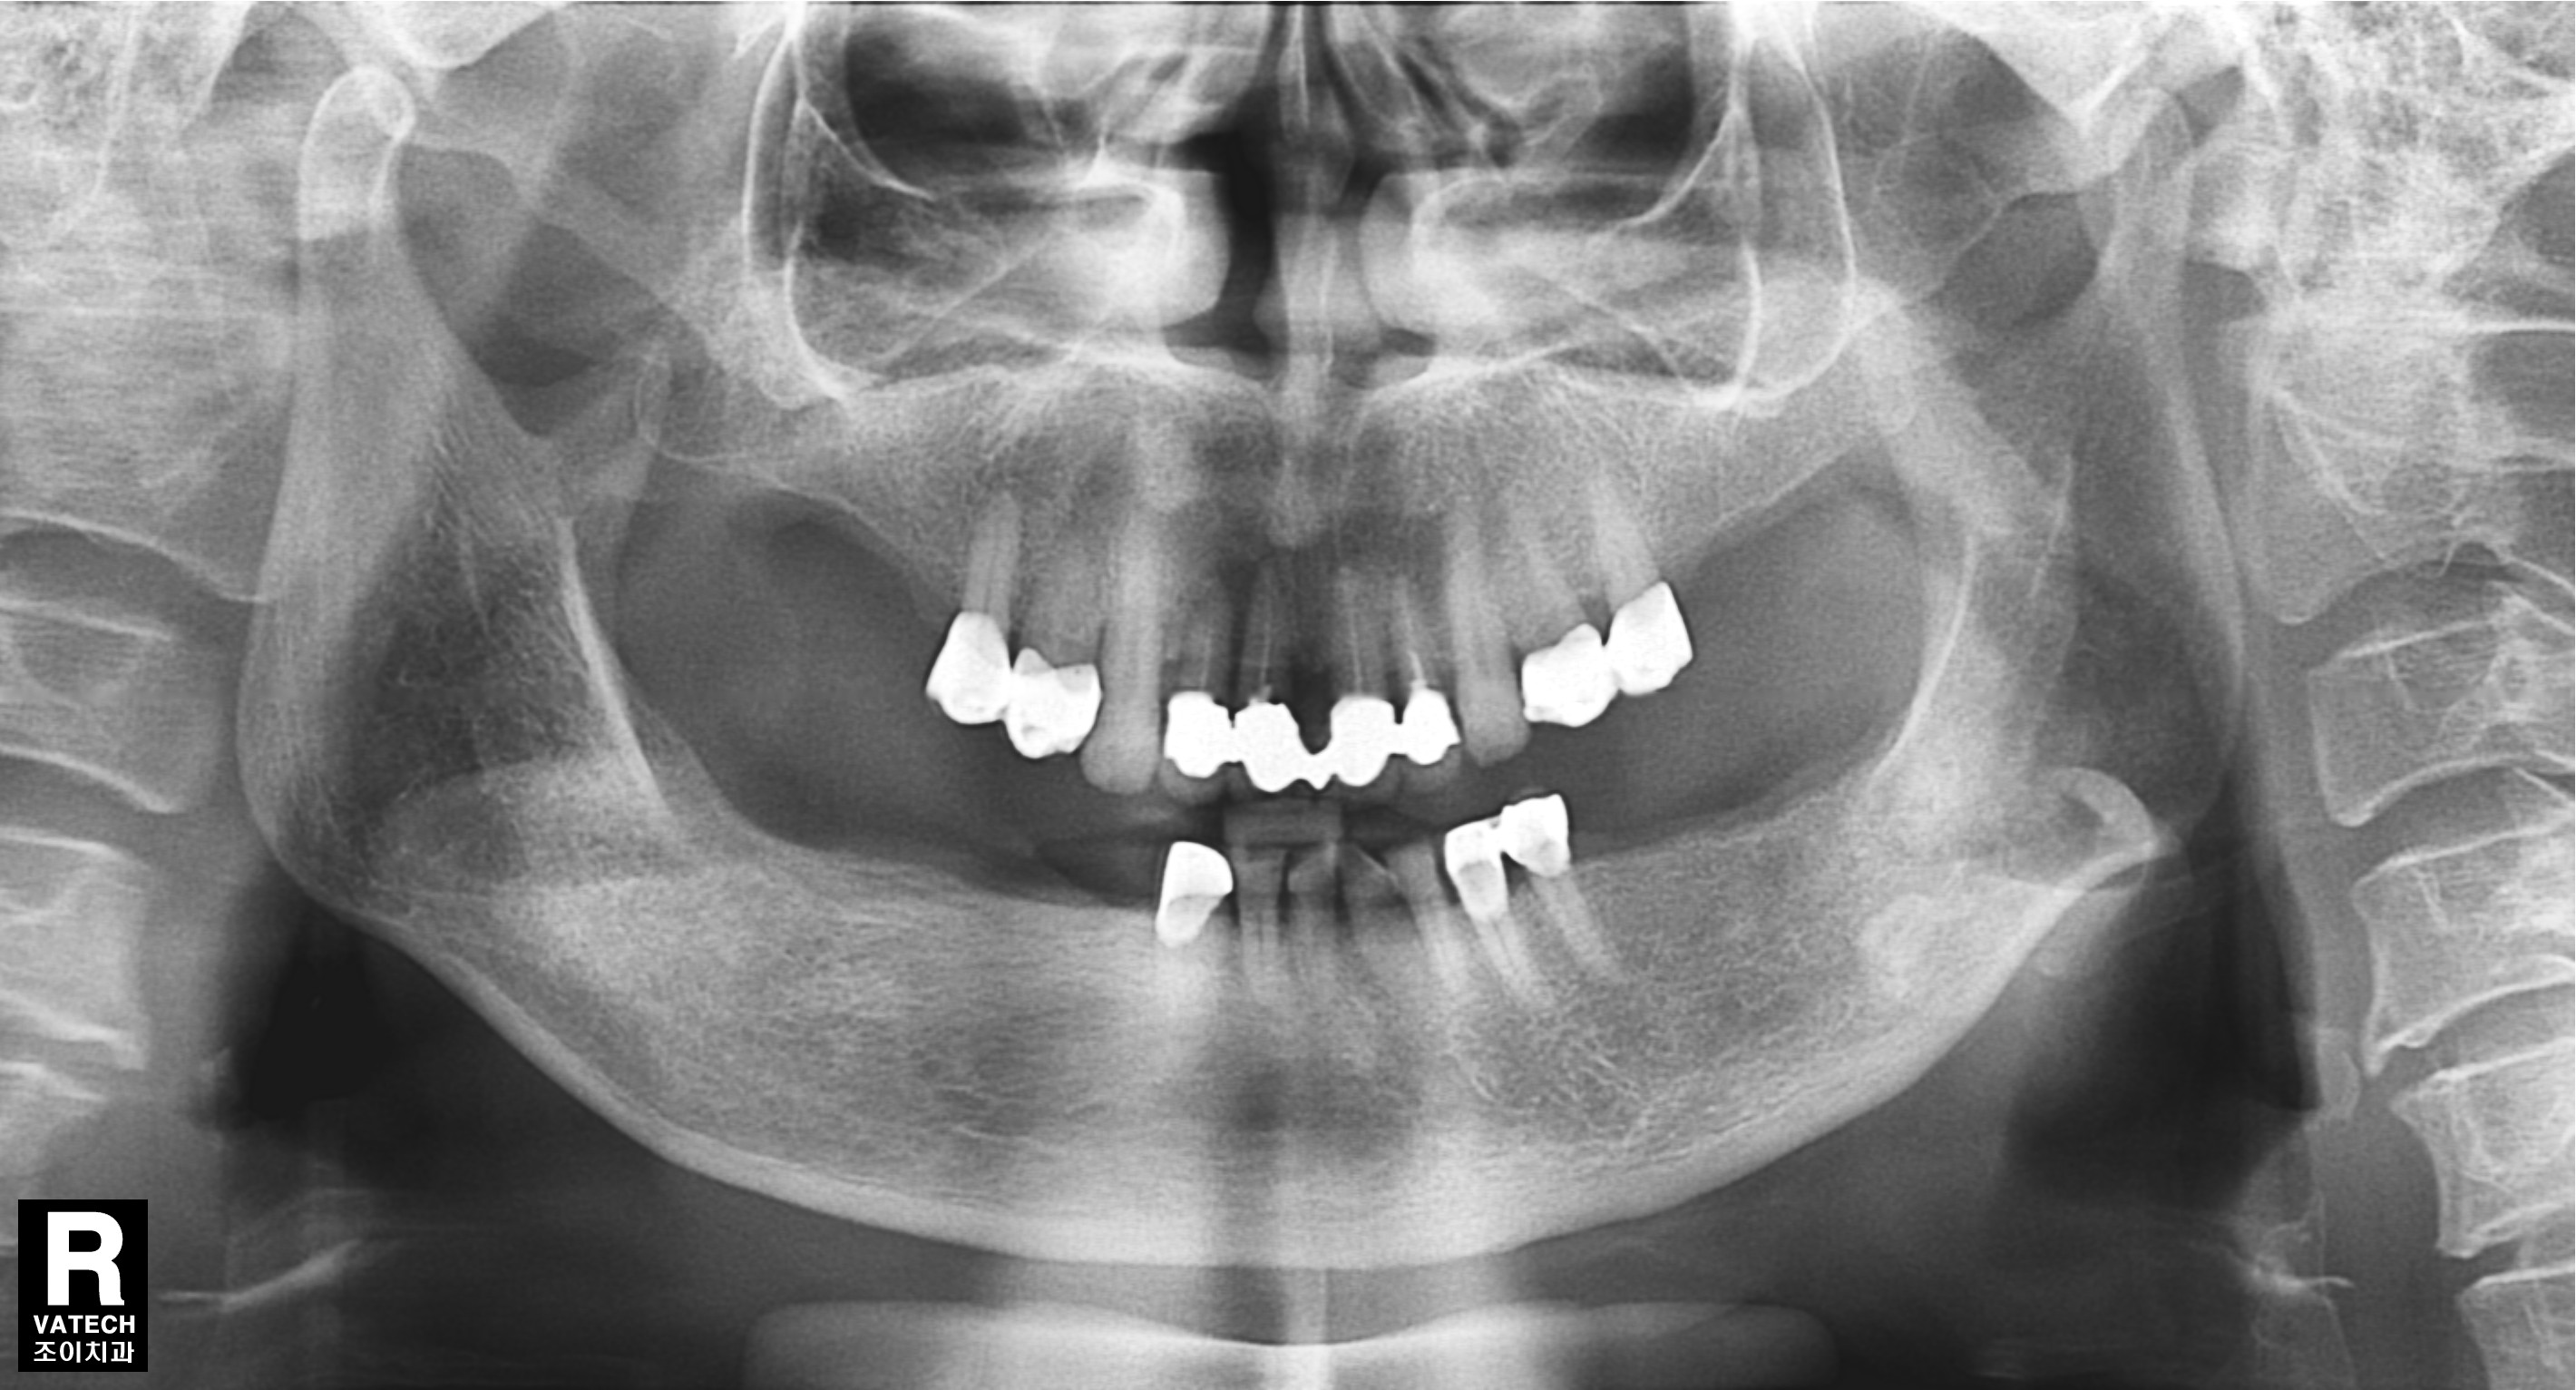

초진과 임플란트 보철 완성 직후 그리고 7년 경과 후 사진의 비교입니다.

또한 임플란트의 사용과 유지 관리에 있어서도 반드시 정기적으로 치과를 방문하여 적절한 관리를 받아야 합니다. 사진에서는 7년이 경과한 후에도 치조골의 흡수 없이 잘 유지되고 있는 상태를 관찰할 수 있습니다.